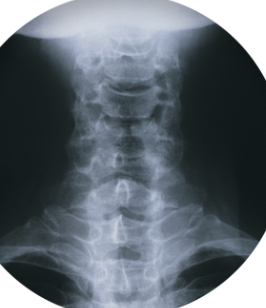

목 디스크는 경추 부위의 디스크가 손상되어 디스크 내부의 젤류 물질이 주변 조직으로 누출되는 질환입니다. 이로 인해 디스크의 충격 흡수 기능이 감소하고 인근 신경이 압박되어 목의 통증, 저림 혹은 근육 약화 등의 증상이 발생할 수 있습니다. 주로 고령자 및 만성적인 목 부하를 받는 사람들에게 발생하며, X-ray, MRI, CT 등의 영상진단을 통해 확인할 수 있습니다. 치료는 약물치료, 물리치료, 수술 등이 있으며, 예방을 위해서는 올바른 자세 유지, 목 운동, 근력강화 운동 등이 필요합니다.